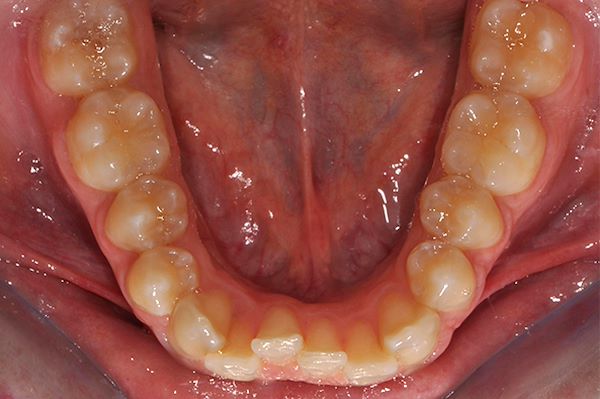

Paziente 29 anni, vuole risolvere il disallineamento inferiore senza però mettere l’apparecchio fisso vestibolare.

E’ stata curata con Invisalign sia all’arcata superiore che all’arcata inferiore, per 1 anno e 4 mesi.